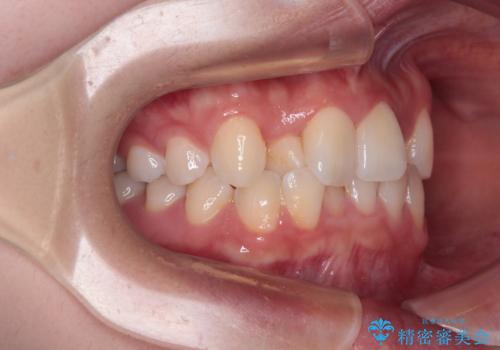

前歯のクロスバイト 裏側に隠れた歯をワイヤー装置で短期間治療

- 上顎前歯のクロスバイトを気にして来院された患者様です。

装置の外見を気にしていましたが、短期間で治療を終えることができるだろうと伝えると、安価であるメタルブラケットを選択されました。